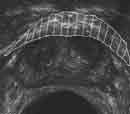

На Рис. 4 представлены эхограммы одного больного — трансабдоминальное и эндовезикальное исследование. Трансабдоминальное сканирование в данном случае не позволяет судить о глубине инвазии, а при эндовезикальном исследовании выявлена начинающаяся инвазия мышечного слоя, причем место инвазии визуализируется как гипоэхогенный участок на фоне гиперэхогенной мышечной ткани (стадия Т2а). Более четко визуализируется инвазия глубокого мышечного слоя (стадия Т2в) (Рис. 5).

Рис. 4. Рак мочевого пузыря стадия Т2а (стрелкой указана начинающаяся инвазия мышечного слоя).

(Слева) Трансабдоминальное сканирование.

(Справа) Эндовезикальное сканирование.